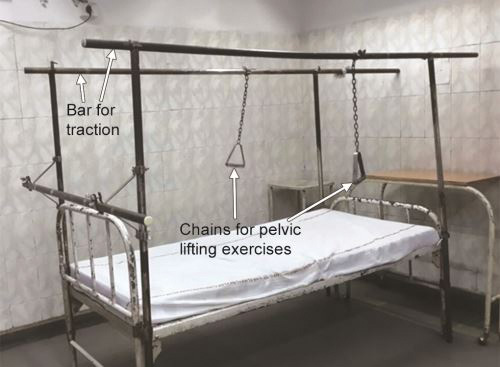

TRACTION

Traction is defined as the application of a continuous, well-sustained pulling force on a limb or muscle group in order to achieve a normal anatomical orientation and correction of bony deformity which occurred due to the fracture or dislocation. Traction relieves pain by counteracting the muscle spasm and allows limb to rest in functional position. Commonly used traction systems in orthopedics are listed in Table 1.10.

Countertraction is the pull acting to offset or oppose primary traction force used for the reduction and to maintain the reduction. Depending on the force providing countertraction the traction may be:

Sliding/Balanced (Fig. 1.31): Where the countertraction is applied by the horizontal component of body weight. Body is kept at an angle by raising the foot end of the bed and gravity/weight of the patient provides the countertraction. Roughly one inch elevation is required for each pound of traction weight.